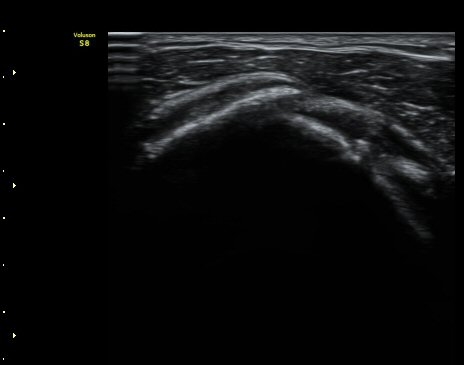

¾î±ú ¾Õ À̵ιڱ٠Ⱦ´Ü¸é°Ë»ç¿¡¼­ ÀÌºÎ¹Ú±Ù°Ç °í¶û ¾Æ·¡ ºÎÀ§¿¡¼­ À̵ιڱ٠ÀåµÎ ÁÖÀ§¿¡

¼ö¾×Àú·ù°¡ °üÂûµÈ´Ù(±×¸² 1, 2). °ß°©ÇÏ±Ù°Ç Á¾´Ü¸é°Ë»ç¿¡¼­ °ß°©ÇϱٰÇÀÇ °üÀý³»ºÎÀ§(±×¸² 3)